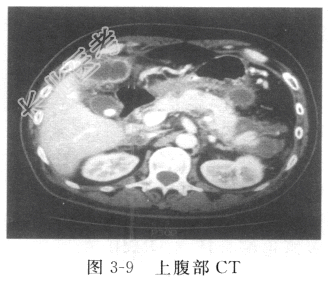

- [材料题] 患者男性,58岁,因“中上腹剧烈疼痛伴呕吐1天”入院。入院前1天患者突然出现中上腹剧烈疼痛,呈持续性、刀割样,伴腹张、频繁呕吐,呕吐物为未消化食物及黄色液体,呕吐后腹痛无缓解,无发热、畏寒,无眼黄、尿黄及皮肤黄染,无呕血、黑粪。外院予禁食、胃肠减压、抗感染、抑酸、抑酶、镇痛等治疗,效果不佳,腹胀进行性加重,伴停止排便、排气。查体:一般情况差,生命体征平稳,蜷曲体位,胃管通畅在位,引流出咖啡色液体。皮肤、巩膜无黄染,心肺泰及阳性体征。腹膨隆,未见胃肠型,腹肌紧张,拒按,全腹部压痛明显,伴反跳痛,腹部来拥及包块,肝脾触诊不满意,墨菲征检查不配合,叩诊星鼓音,移动性浊音可疑阳性,肝肾区无叩击痛;听诊1min肠鸣音消失。双下肢无水肿。辅助检查:血常规WBC 22.9×10⁹/L,N%81.6%;血生化:ALT 220U/L,AST 263U/L,血淀粉酶>4800U/L,GLU 9.5mmol/L,Ca²⁺2.4mmol/L;彩超:胆囊结石、胆囊炎;胆总管、主胰管扩张。入院上腹部CT(图3-9)示胰腺体积弥漫性肿大,胰周见大量絮样渗出液,左侧肾周筋膜增厚;CT考虑急性胰腺炎,胆囊结石、胆囊炎,腹腔积液,双肺炎症,双侧胸腔积液。上腹部MRI+MRCP:胆总管轻度扩张,胆总管下端隐约可见充盈缺损。